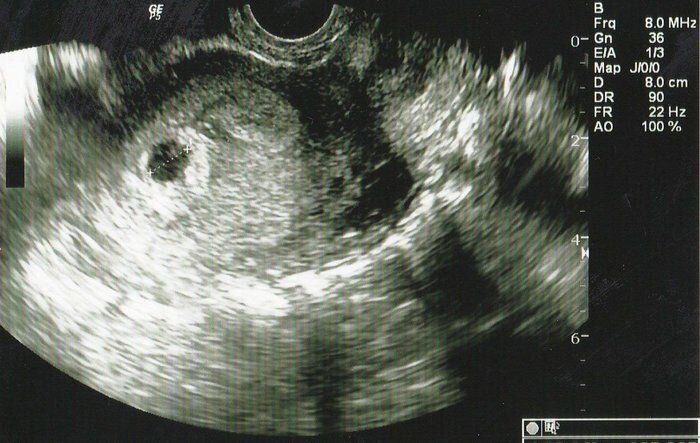

ちゃじゅびさんの妊娠4週目のエコー写真

結婚10年目にしてやってきた待望の赤ちゃん。初めてのエコー画像は「ここに本当に赤ちゃんがいるの?」というようなものでした。初期の流産を経験しているので、「何かあったらすぐに連絡するように」と、当時は主治医の先生の携帯番号がエコー写真の下に添えてありました。